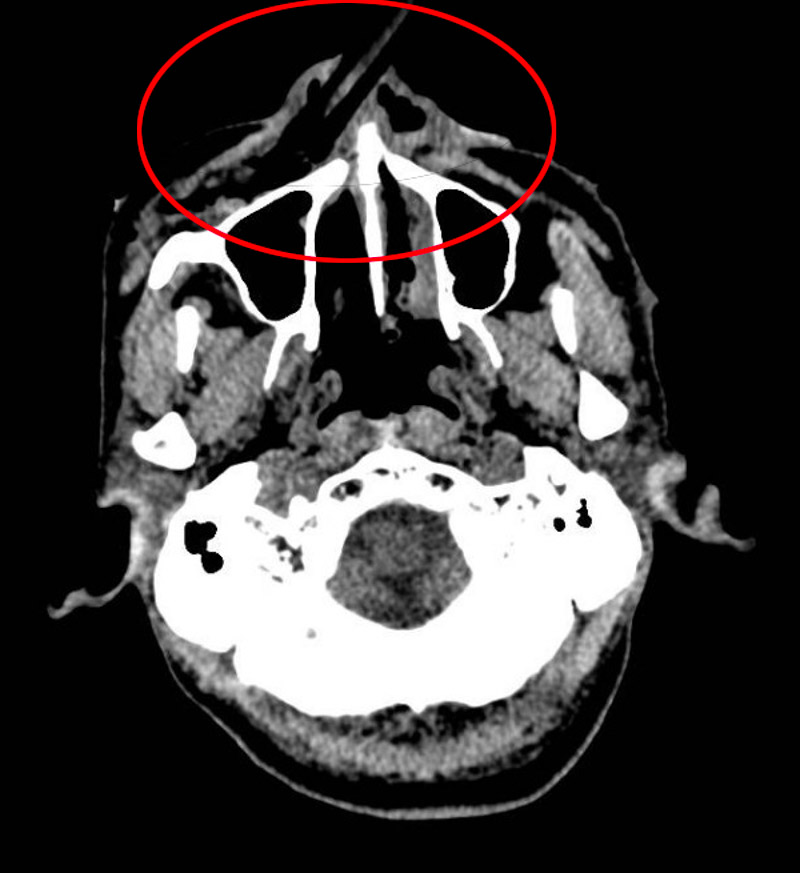

術(shù)中發(fā)現(xiàn),竹棍由鼻尖處穿通鼻中隔插入鼻腔,貫穿鼻底黏膜,直達(dá)上頜竇前壁。口腔科主任宋勇博士小心翼翼地將竹棍拔出,此時(shí),仍有大量竹棍碎屑?xì)埩粼诒乔粌?nèi)。由于竹棍在進(jìn)入鼻腔后發(fā)生了折斷,很多碎屑插入軟組織,傷口深、視野差,清理難度大。如果異物清除不干凈,會(huì)在創(chuàng)口內(nèi)持續(xù)發(fā)炎,導(dǎo)致二次手術(shù)。